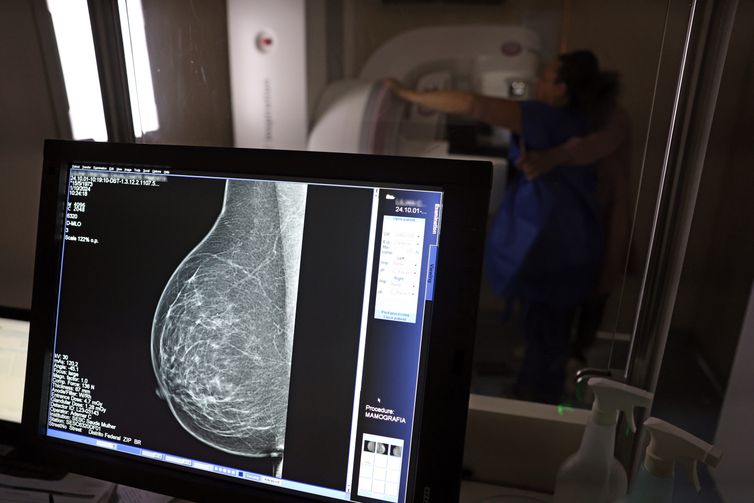

Falta de acesso a mamógrafos limita prevenção do câncer de mama

Atlas da Radiologia mostra que país tem baixa cobertura de mamografias, 24%. O ideal, recomendado pela OMS, é de 70%.

No mês de conscientização sobre o câncer de mama, um relatório destaca a importância de acesso igualitário ao rastreamento e tratamento da doença. Segundo o Atlas da Radiologia no Brasil, do Colégio Brasileiro de Radiologia e Diagnóstico por Imagem (CBR), o acesso aos mamógrafos ainda é um desafio.

O país tem 6.826 equipamentos registrados, sendo 96% em funcionamento. Metade deles está disponível no Sistema Único de Saúde (SUS), responsável por atender 75% da população. Isso equivale a 2,13 mamógrafos por 100 mil habitantes dependentes do SUS.

Na saúde suplementar, que cobre 25% da população, o cenário é mais favorável: 6,54 aparelhos por 100 mil beneficiárias, quase o triplo da rede pública. O Acre exemplifica essa disparidade — são 35,38 mamógrafos por 100 mil habitantes na rede privada, contra 0,84 no SUS.

O Brasil tem uma cobertura muito baixa de mamografias: 24%. O ideal recomendado pela Organização Mundial da Saúde é de 70%. Mesmo em lugares como o estado de São Paulo, que tem a maior concentração de mamógrafos do país, a taxa gira em torno de 26%.